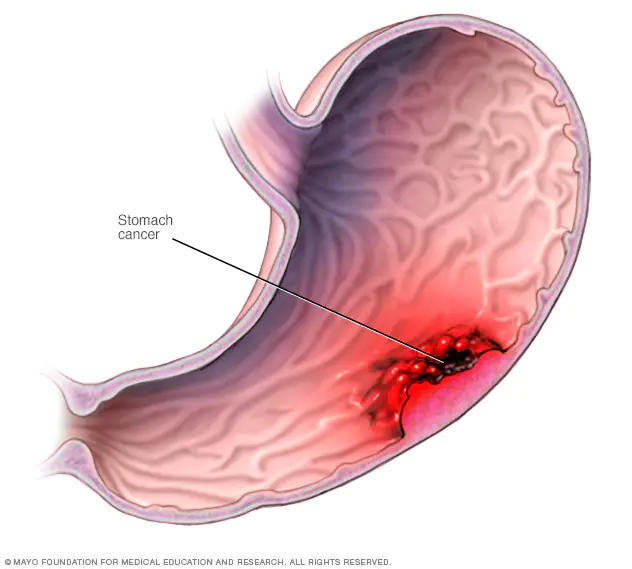

سرطان معده : سرطان معده که سرطان معده نیز نامیده می شود، رشد سلول هایی است که از معده شروع می شود. معده در قسمت میانی بالای شکم، درست زیر دنده ها قرار دارد. معده به تجزیه و هضم غذا کمک می کند.

سرطان معده ممکن است در هر قسمتی از معده رخ دهد. در بیشتر نقاط جهان، سرطان معده در قسمت اصلی معده اتفاق می افتد. این قسمت را بدن معده می نامند. در ایالات متحده، سرطان معده بیشتر از محل اتصال معده به مری شروع می شود. این قسمتی است که در آن لوله بلندی که غذایی را می بلعید به معده می رسد. لوله ای که غذا را به معده می رساند، مری نامیده می شود.

جایی که سرطان در معده شروع می شود یکی از عواملی است که ارائه دهندگان مراقبت های بهداشتی هنگام تهیه یک برنامه درمانی به آن فکر می کنند. سایر عوامل ممکن است شامل مرحله سرطان و نوع سلول های درگیر باشد. درمان اغلب شامل جراحی برای برداشتن سرطان معده است. درمان های دیگر ممکن است قبل و بعد از جراحی استفاده شود.

اگر سرطان فقط در معده باشد، درمان سرطان معده به احتمال زیاد موفقیت آمیز است. پیش آگهی برای افراد مبتلا به سرطان معده کوچک بسیار خوب است. بسیاری می توانند انتظار درمان داشته باشند. بیشتر سرطان های معده زمانی پیدا می شوند که بیماری پیشرفته باشد و احتمال درمان آن کمتر است. سرطان معده که از طریق دیواره معده رشد می کند یا به سایر قسمت های بدن گسترش می یابد، درمان آن سخت تر است.